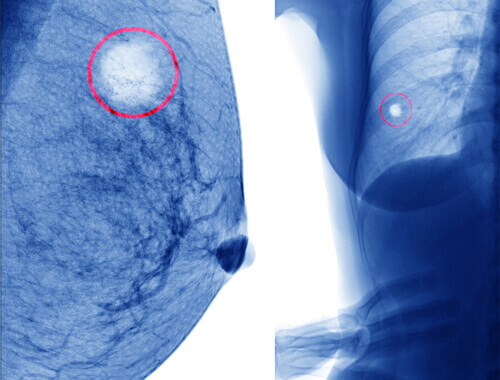

A mammary cyst is a collection of liquid on the inside of the breast. Therefore, it’s a small sack, generally about the size of a chickpea or smaller, which usually contains liquid.

While the majority of mammary cysts are filled with liquid, there are also benign cysts that are more solid.

There’s another type of cyst called a fibroadenoma. These tend to be symptomless and painless. Usually, you can discover them during a breast exam by feeling a small, hard, moveable lump in the breast.

It will generally feel either smooth or a bit rough when caused by a fibroadenoma with lobes when you touch it. It will move freely around the breast when you touch it. F

ortunately, they are also benign. Fibroadenomas occur when there is excessive growth of mammary tissue. Also, although they may be confused with the mammary cysts that we described above, they are different.